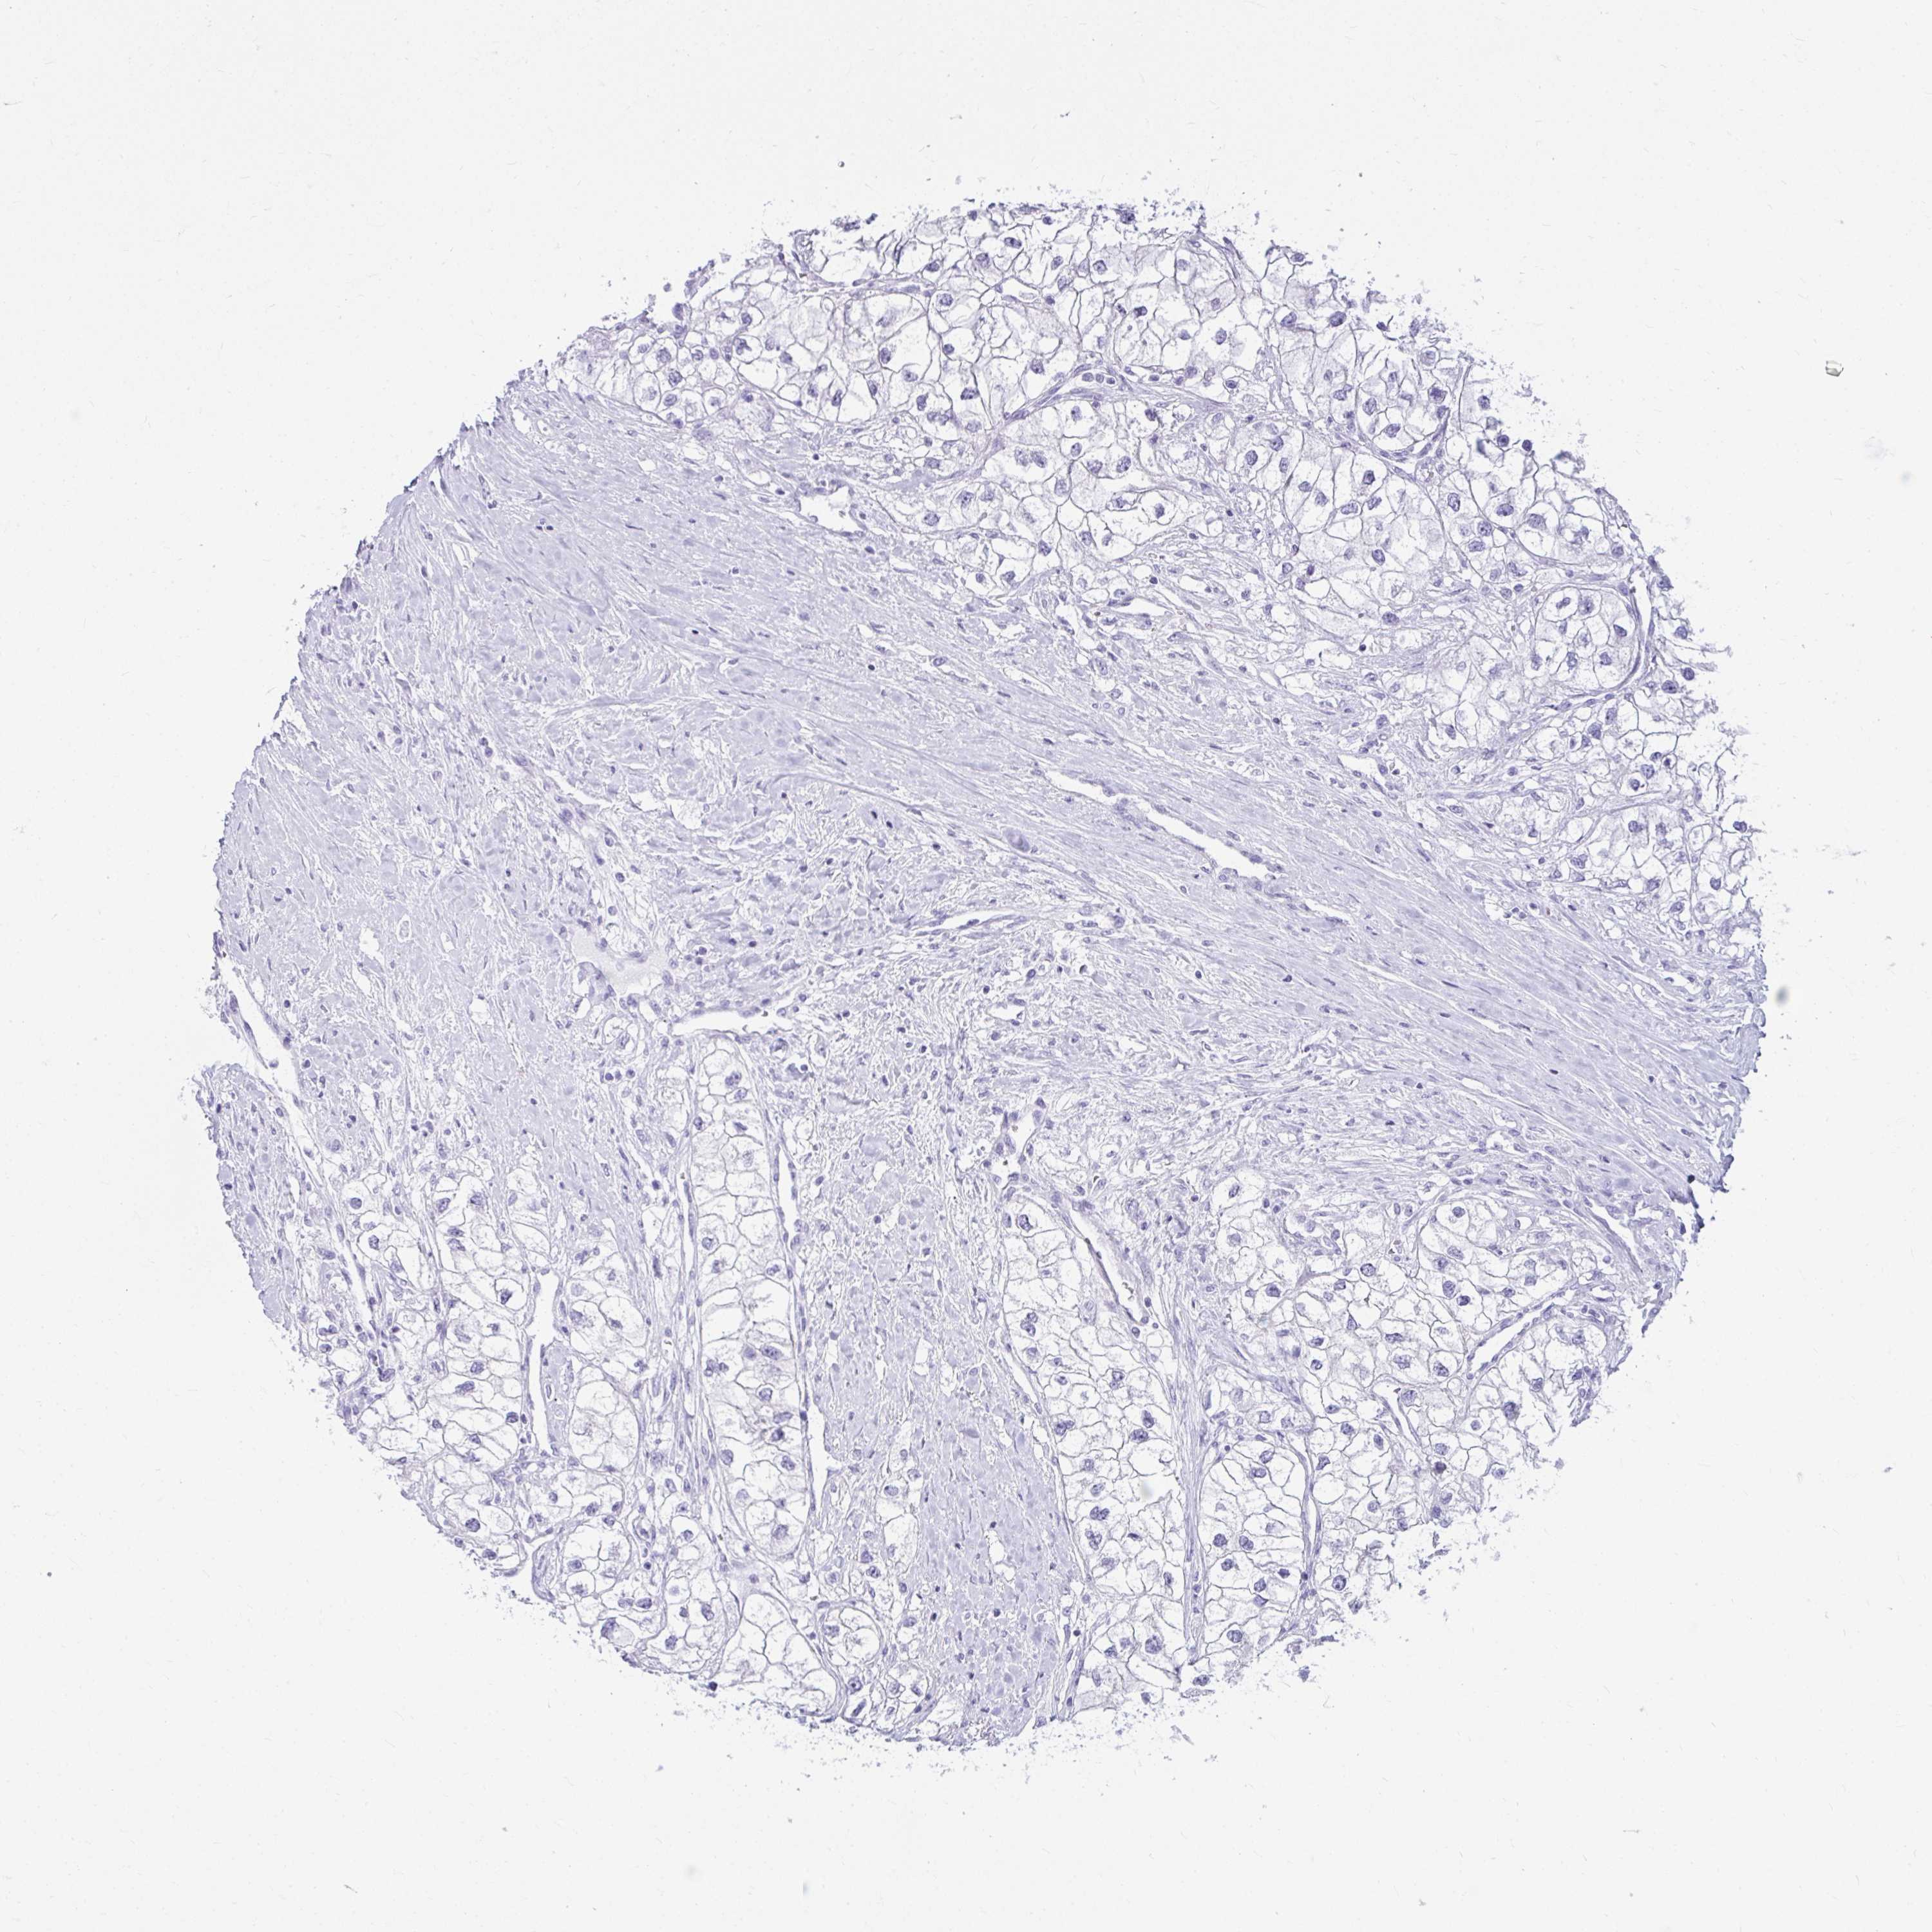

KIDNEY RENAL PAPILLARY CELL CARCINOMA (TCGA) - Interactive survival scatter ploti

The Survival Scatter plot shows the clinical status (i.e. dead or alive) for all individuals in the patient cohort, based on the same data that underlies the corresponding Kaplan-Meier plots. Patients that are alive at last time for follow-up are shown in blue and patients who have died during the study are shown in red.

The x-axis shows the expression levels (FPKM) of the investigated gene in the tumor tissue at the time of diagnosis. The y-axis shows the follow-up time after diagnosis (years). Both axes are complimented with kernel density curves demonstrating the data density over the axes. The top density plot shows the expression levels (FPKM) distribution among dead (red) and alive patients (blue). The right density plot shows the data density of the survived years of dead patients with high and low expression levels respectively, stratified using the cutoff indicated by the vertical dashed line through the Survival Scatter plot. This cutoff is automatically defined based on the FPKM cutoff that minimizes the p-score. The cutoff can be changed by dragging the vertical line or by entering a cutoff value in the square labeled "Current cut-off".

Under the Survival Scatter plot the p-score landscape (black curve; left axis) is shown together with dead median separation (red curve; right axis). Dead median separation is the difference in median mRNA expression between patients who have died with high and low expression, respectively. It is calculated as follows: median FPKM expression of dead patients with high expression - median FPKM expression of dead patients with low expression. This is intended to aid the user in visually exploring custom cutoffs and the associated p-scores and dead median separation.

Individual patient data is displayed and can be filtered by clicking on one or more of the category buttons on the top of the page. Categories describing expression level and patient information include: high, low, alive, dead, female, male and tumor stages. The scale of the x-axis can be toggled between linear and log-scale by clicking on the "x log" button. Mouse-over function shows TCGA ID, patient information and mRNA expression (FPKM) for each patient.

& Survival analysisi

Kaplan-Meier plots summarize results from analysis of correlation between mRNA expression level and patient survival. Patients were divided based on level of expression into one of the two groups "low" (under cut off) or "high" (over cut off). X-axis shows time for survival (years) and y-axis shows the probability of survival, where 1.0 corresponds to 100 percent.

CLGN is not prognostic in Kidney Renal Papillary Cell Carcinoma (TCGA)

Best expression cut offi

Based on the FPKM value of each gene, patients were classified into two groups and association between prognosis (survival) and gene expression (FPKM) was examined. The best expression cut-off refers the FPKM value that yields maximal difference with regard to survival between the two groups at the lowest log-rank P-value. Best expression cut-off was selected based on survival analysis .

When clicking on this number, the vertical dashed line indicating cut-off, the interactive survival plot, and the Kaplan-Meier curve will be adjusted to show results based on the best expression cut-off.

: 3.13